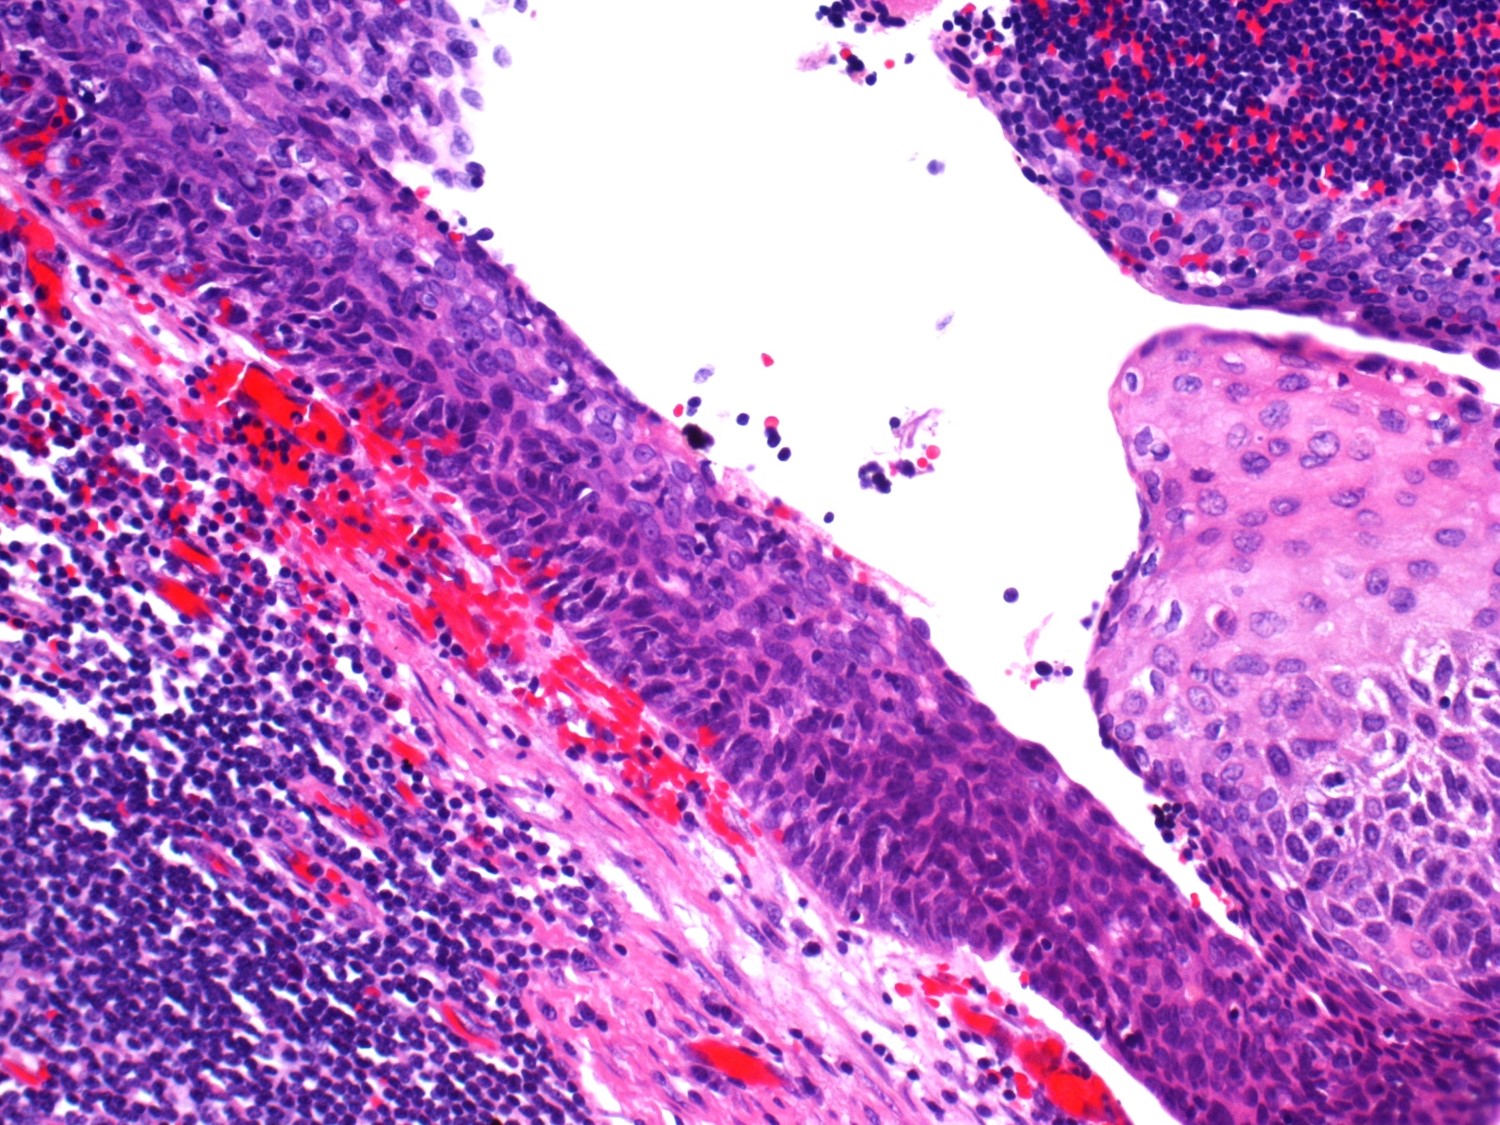

Case history

71-year-old male veteran presenting with hematuria. Two ulcerated lesions identified...